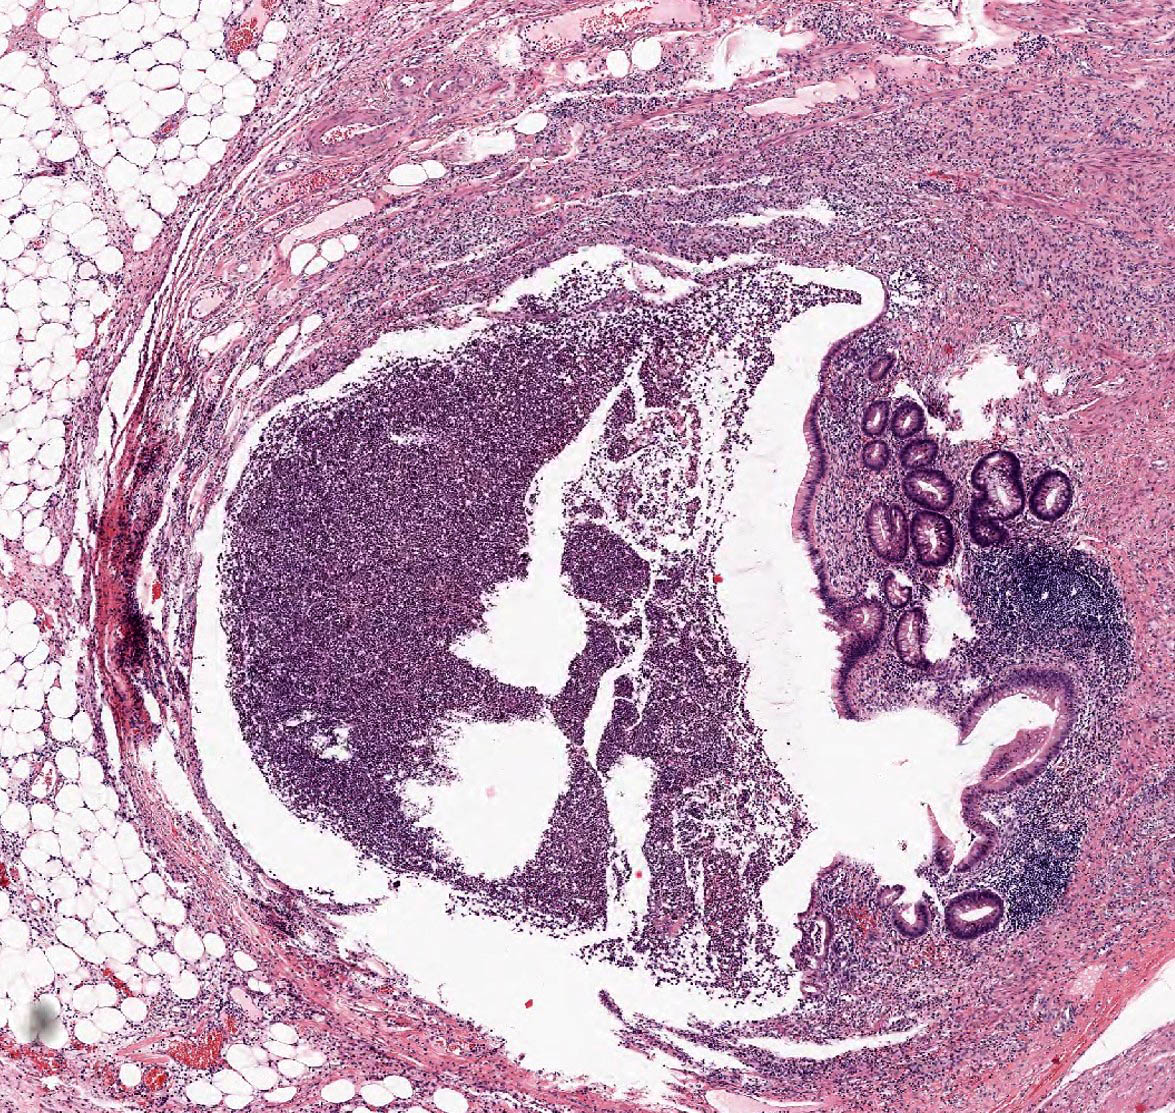

Acute Appendicitis

- 1Transmural neutrophilic inflammation

- 2Mucosal ulceration and cryptitis

- 3Luminal obstruction (faecolith or lymphoid hyperplasia)

Acute appendicitis is acute inflammation of the vermiform appendix, most commonly caused by luminal obstruction (faecolith or lymphoid hyperplasia) leading to bacterial overgrowth, mucosal ulceration, and transmural inflammation. It is the commonest surgical emergency of the abdomen.

- Hyperplastic lymphoid follicles causing luminal obstruction

- Transmural neutrophilic infiltration of the appendiceal wall

- Mucosal ulceration overlying the obstructed segment